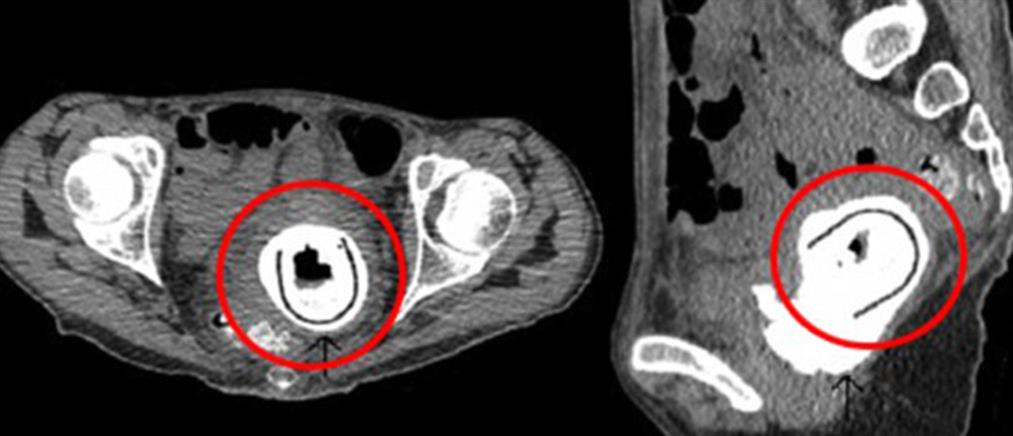

Το παράκαναν και ο άντρας χρειάστηκε ιατρική παρέμβαση για να του αφαιρεθεί το σεξουαλικό βοήθημα…